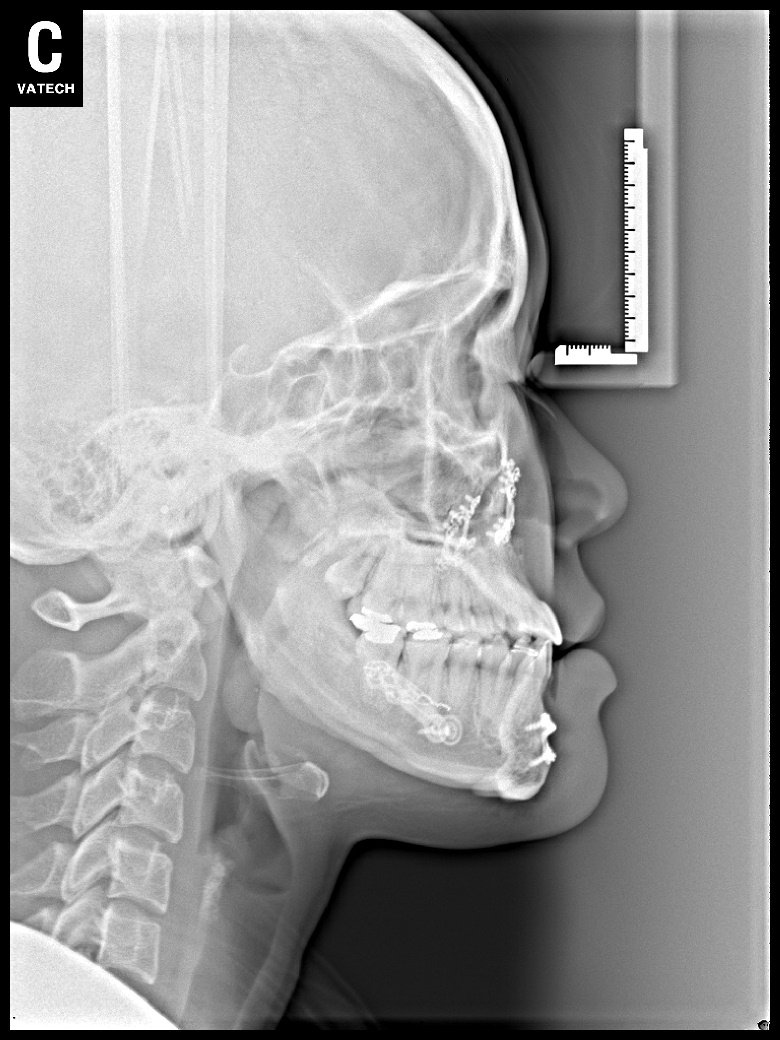

치료 후 사진입니다.